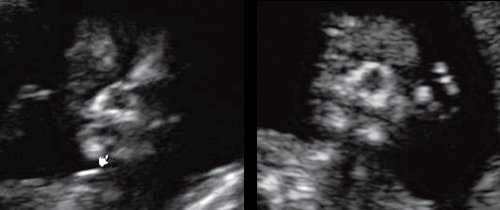

При эхографии в срок 13 недель 3 дня фетометрические параметры плода соответствовали гестационной норме, толщина воротникового пространства составила 1,5 мм; длина костей носа - по 2,5 мм. При трансвагинальном сканировании были обнаружены: затылочное энцефалоцеле размерами 7,4х3,5х3,7 мм (рис. 1), полидактилия кистей (рис. 2), увеличенные кистозно-измененные почки: правая - 28,5х21,3 мм; левая - 26,4х18,7 мм (рис. 3). Объем амниотической полости был нормальным для данного срока.

• Конечности:

о Постаксиальная полидактилия:

- Добавочный палец может быть уменьшен или искривлен

- Обычно поражены все 4 конечности, однако данный признак является наименее устойчивым

- Визуализация на фоне маловодия может быть затруднена